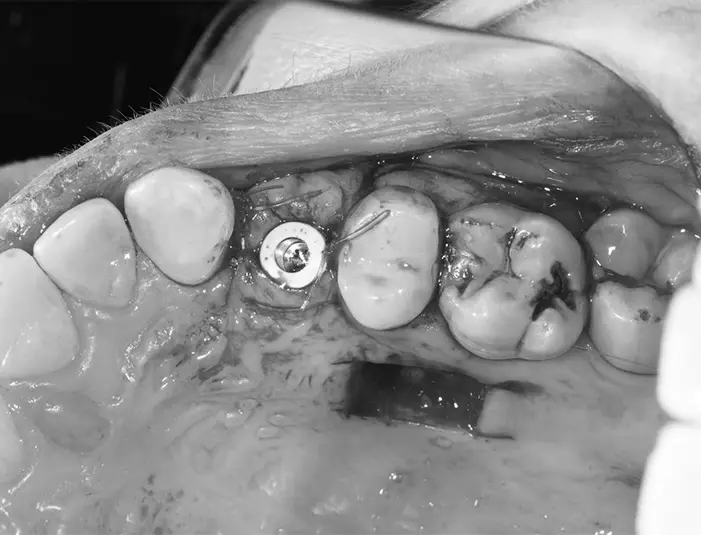

4) Placing the graft at the implant site:

The graft was secured into the area of soft‑tissue deficiency to increase thickness and improve the gum contour.

5) Implant placement and provisionalization:

A dental implant post was placed into the jawbone at the missing upper premolar site. A temporary crown/provisional was fitted over the implant. The provisional is shaped so the gum heals around it in a natural, scalloped form—this is the emergence profile.